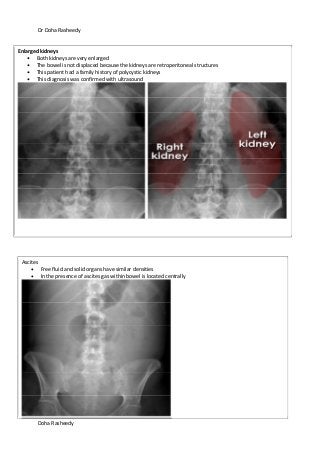

Enlarged kidneys

Both kidneys are very enlarged

The bowel is not displaced because the kidneys are retroperitoneal structures

This patient had a family history of polycystic kidneys

This diagnosis was confirmed with ultrasound

Ascites

Free fluid and solid organs have similar densities

In the presence of ascites gas within bowel is located centrally